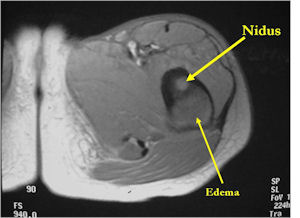

MRI:

- MRI should be performed with gadolinium if possible. The nidus should enhance with gadolinium

- An osteoid osteoma on MRI may mimic findings of a malignant tumor such as Ewing’s sarcoma or osteomyelitis because of the presence of marrow and soft tissue edema that can be extensive and make it difficult to discern a nidus.

- CT is more useful for detecting the nidus if there is extensive edema

- Osteoid Osteomas are Intermediate intensity on T1

- High intensity on T2 in areas of nidus and surrounding edema

- Reactive marrow edema may obscure the lesion on T2

- MRI is good for detecting synovitis and joint effusion with intraarticular osteoid osteomas